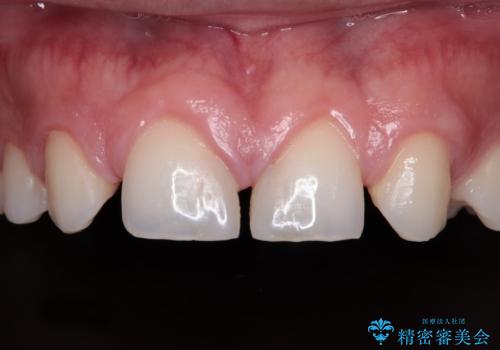

[ セラミック治療 ] 仮歯で放置した前歯をきれいにしたい

担当医 大元洋佑